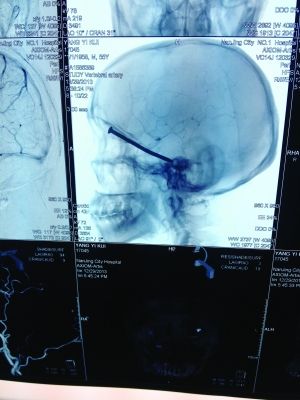

CT投影

前幾天,市民楊先生在家翻新地板時(shí),眼中突然飛入“異物”。去醫(yī)院檢查,發(fā)現(xiàn)這“異物”竟是一根長(zhǎng)達(dá)8厘米的鐵釘!好在鐵釘錯(cuò)開(kāi)了楊先生頭部的各種大血管,醫(yī)生得以順利將其取出。

CT投影結(jié)果,把大家嚇了一跳:楊先生腦子里居然有一根長(zhǎng)釘,從眼眶一直“伸”到了接近后腦勺的位置!鐵釘細(xì)長(zhǎng)略帶彎曲,長(zhǎng)達(dá)8厘米。根據(jù)推測(cè),鐵釘應(yīng)該是從上眼眶的縫隙中飛入,一直插進(jìn)腦顱中,末端還有一個(gè)小小凸出的釘帽。